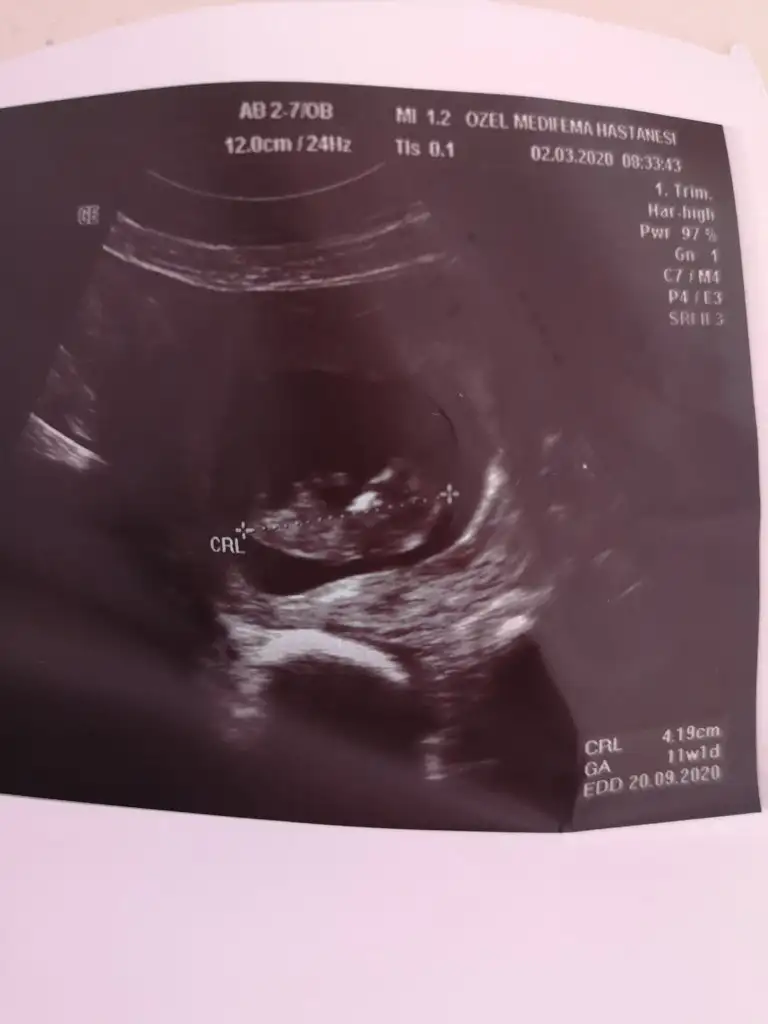

Ben burayı nasıl kaçırmışım.En son ultrason resmimiz 11+3 'ten.Tahmin alabilir miyim arkadaslar